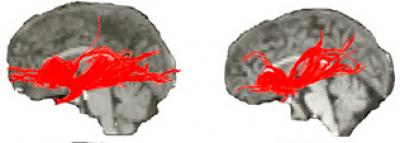

Diffusion tensor imaging, which by detecting the flow of water in nerve fibers can identify and measure the connections between brain areas, showed reduced white matter – the brain's long-distance wiring – between thinking and emotion hubs.

Tracking radioactively-tagged water in order to measure brain blood flow at rest, via positron emission tomography (PET), exposed activity aberrations consistent with the MRI abnormalities. The PET scans also revealed altered functional coupling between the front of the insula and key structures involved in thinking, mood and fear processing. These structural and functional abnormalities in the front of the insula correlated with the Williams syndrome personality profile.